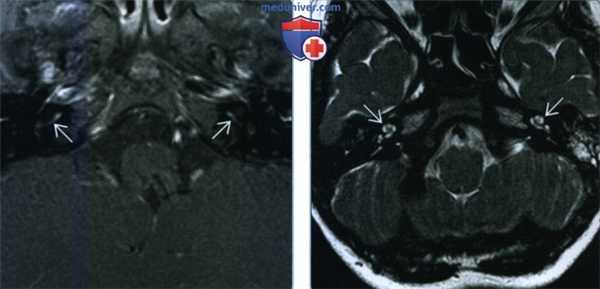

(Слева) При аксиальной МРТ Т1 ВИ С+ FS у годовалого мальчика с перенесенным менингитом и нейросенсорной тугоухостью определяется патологическое контрастирование базального завитка улитки с обеих сторон, сопоставимое с менингогенным лабиринтитом.

(Справа) При аксиальной МРТ Т2 ВИ FSE у пациента с двухсторонним лабиринтитом определяется гиперинтенсивная жидкость (норма) в улитке с обеих сторон. Наличие жидкости с типичным или слегка гипоинтенсивным сигналом позволяет отличить лабиринтит от объемного образования.

(Слева) При аксиальной МРТ Т1 ВИ С+ у пациента с внезапно возникшим головокружением и тугоухостью на фоне вирусного лабиринтита определяется патологическое контрастное усиление завитков улитки и преддверия.

(Справа) При аксиальной МРТ Т1 ВИ С+ определяется контрастирование улитки и внутреннего слухового канала у пациента с двухсторонним отомастоидитом, оталгией, параличом ЧН VII и тугоухостью. Барабанный сегмент ЧН VII в этом примере тимпаногенного лабиринтита также утолщен и накапливает контраст.